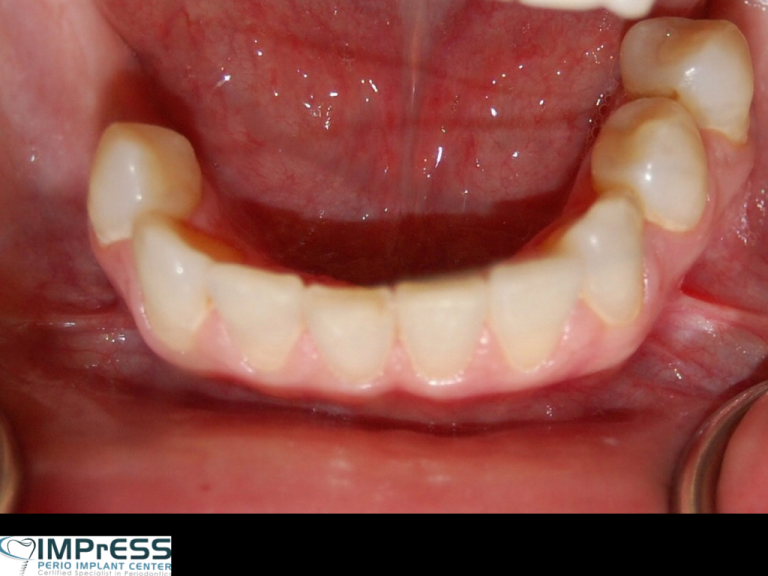

Connective Tissue Gingival Grafting for Gingival Recession